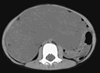

患儿,男,4岁,发现腹部包块1年余。查体:腹膨隆,可及约10 cm×10 cm大小包块,质软,无压痛。CT检查显示:腹腔内有略低密度占位性病变,约6.7 cm×16.7 cm×15.7 cm,密度均匀,腹部肠管受压向左前上腹移位(图1)。病变强化不明显,内见散在血管断面;肠系膜上动脉受压抬高,分支分散(图2)。肿物内可见沿肠系膜走行的血管影。诊断为腹腔内囊性占位——肠系膜淋巴管瘤不除外。

图2 CT三维重建显示:肠系膜上动脉受压上抬(箭头),分支较细,分散走行。, 百拇医药